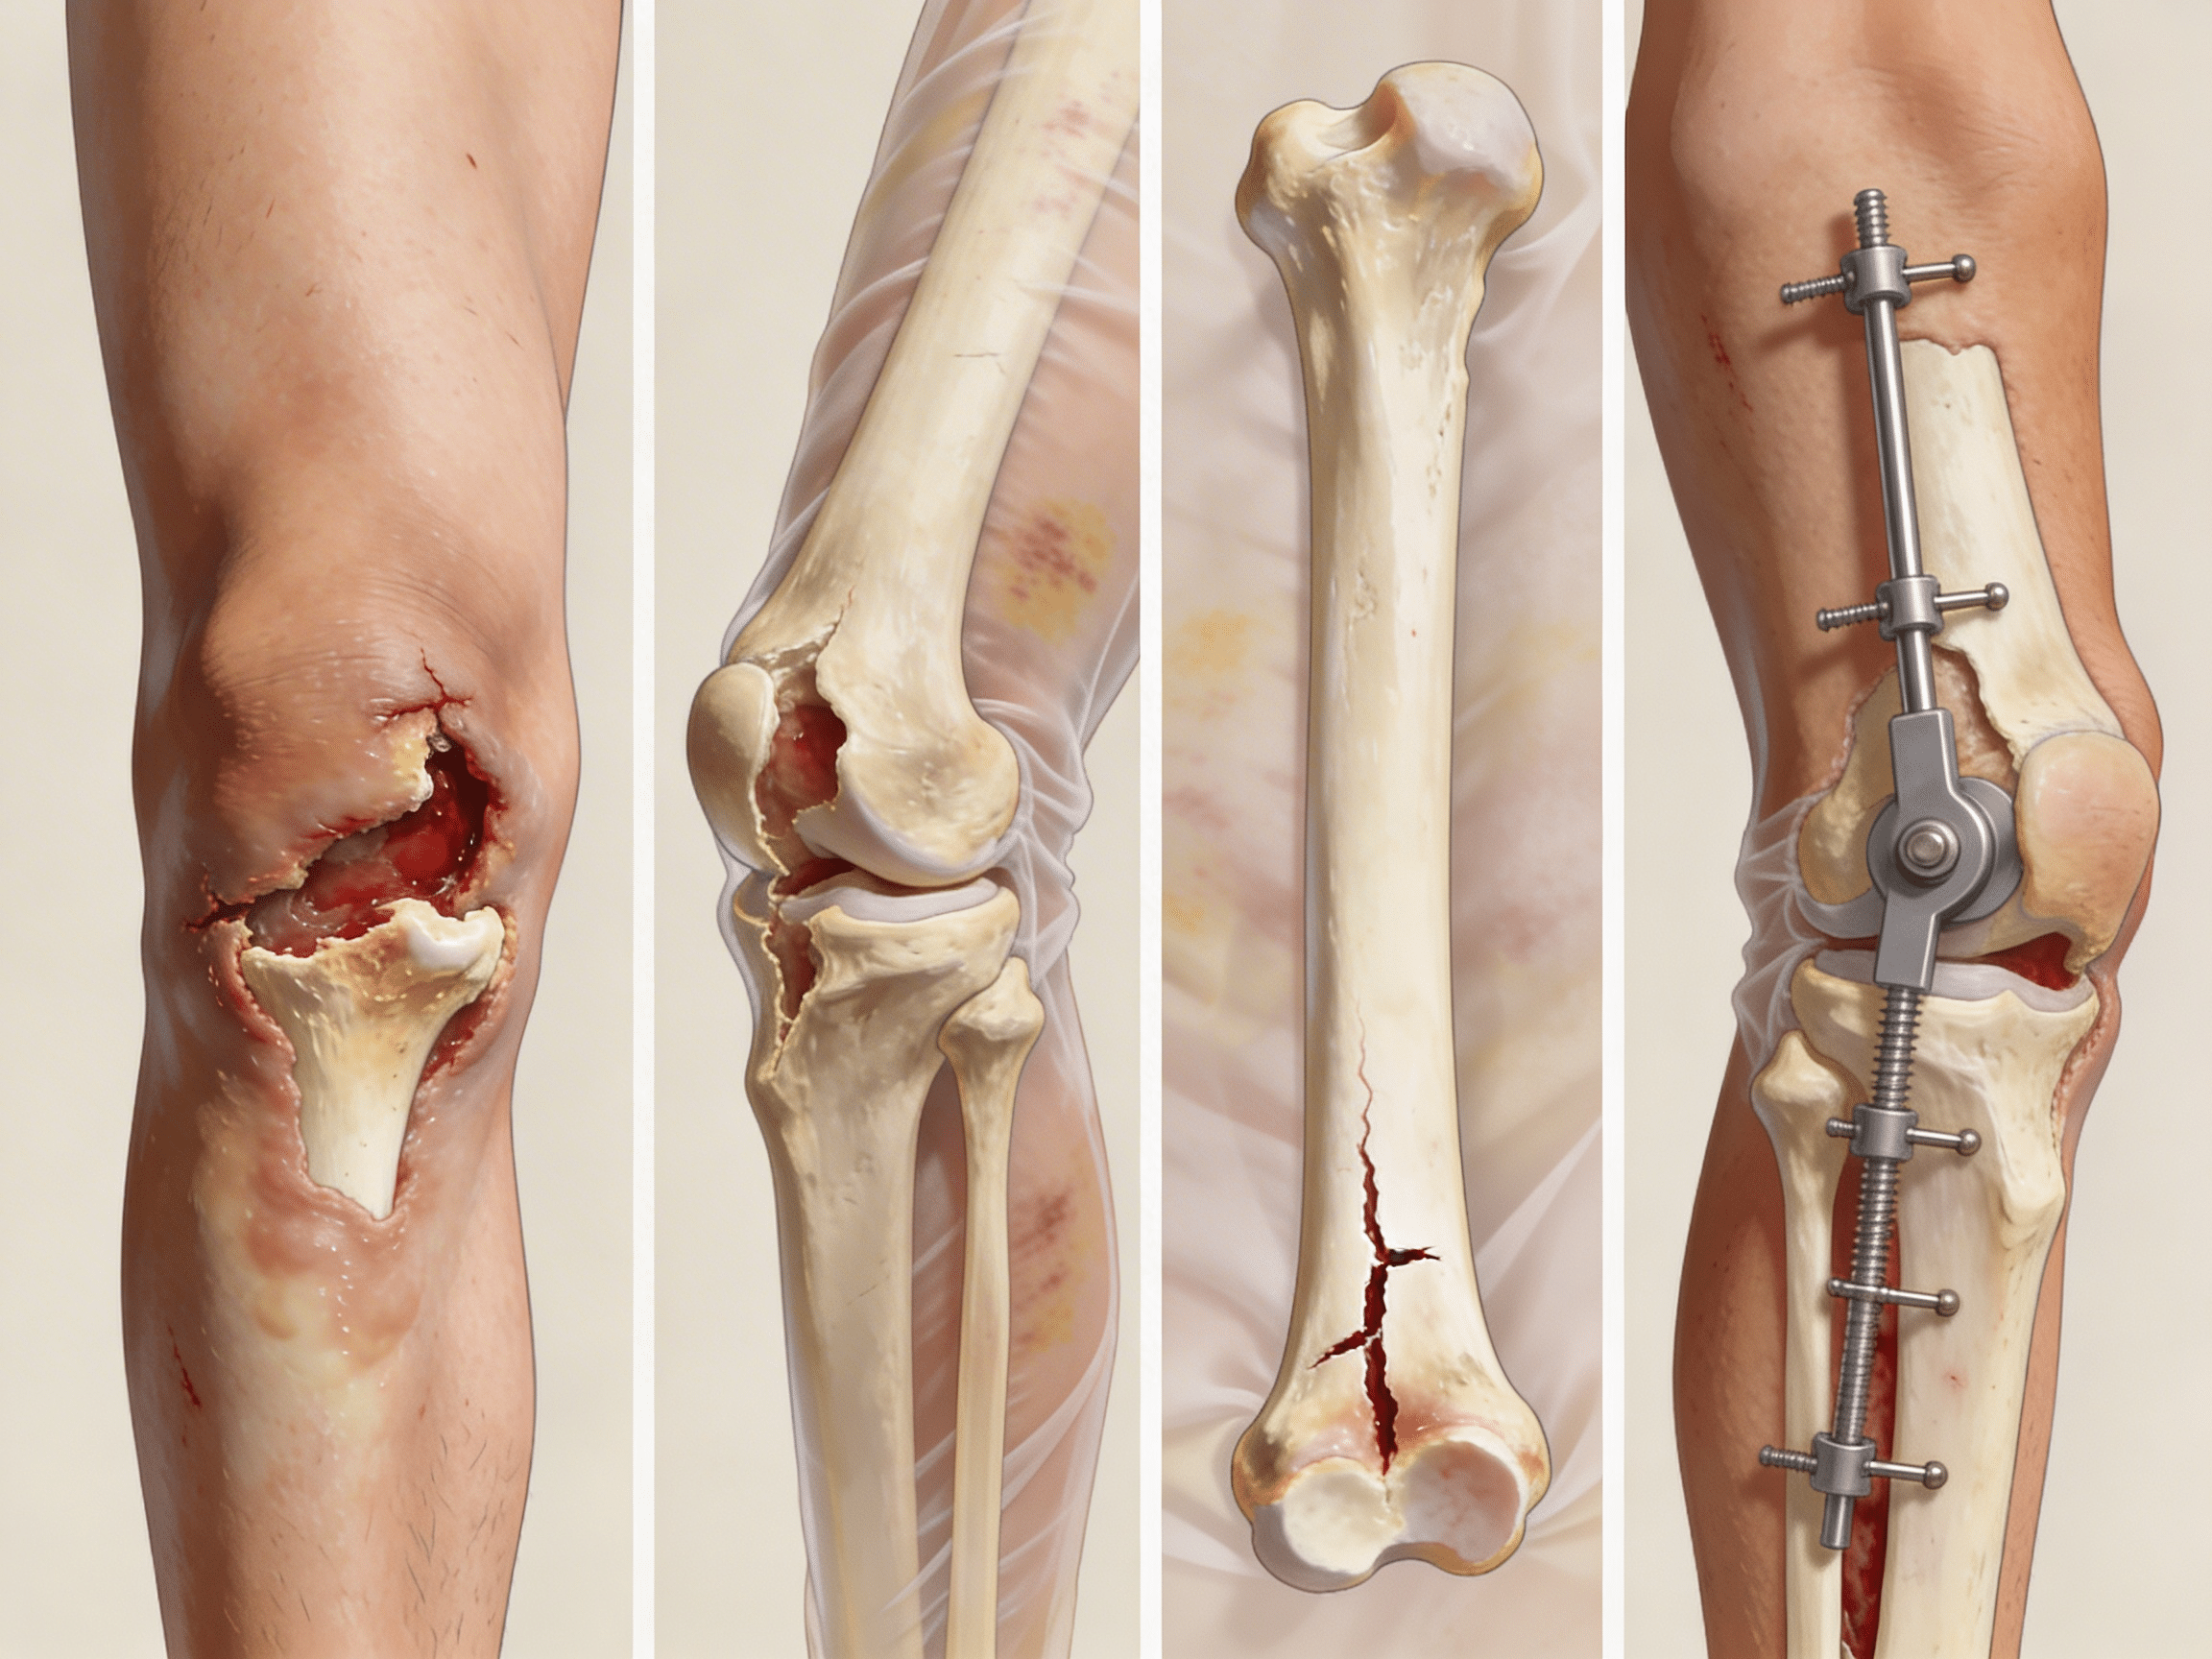

What's the difference between open (compound) and closed fractures?

Open (compound) fractures involve bone breaking through skin creating contaminated wounds requiring immediate IV antibiotics, surgical debridement, and infection prevention protocols. Closed fractures maintain intact skin without open wounds, requiring fracture reduction and stabilization but lower infection risk. Priority ER treats both types immediately, with open fractures receiving emergency irrigation, tetanus prophylaxis, broad-spectrum antibiotics within 1 hour, and urgent orthopedic consultation for operative debridement preventing life-threatening osteomyelitis complications.

According to the American Academy of Orthopaedic Surgeons, approximately 6.8 million fractures occur annually in the United States, with long-bone fractures of the femur, tibia, humerus, and radius comprising 42% of all emergency orthopedic cases[5]. The critical difference between optimal healing and permanent complications often comes down to seeking appropriate open (compound) and closed long-bone fractures care within the first hour of injury. Our orthopedic emergency capabilities include immediate fracture reduction, neurovascular assessment, and direct admission coordination when surgical fixation requires operating room intervention beyond emergency department stabilization.

Open (compound) fractures, neurovascular compromise, femoral fractures, multiple trauma, compartment syndrome signs. Requires immediate ER treatment with surgical consultation to prevent infection, limb loss, or permanent disability.

Closed displaced fractures, severe pain, inability to bear weight, significant swelling, suspected long-bone fracture. Needs emergency evaluation within 1-2 hours for proper reduction, splinting, and orthopedic follow-up planning.